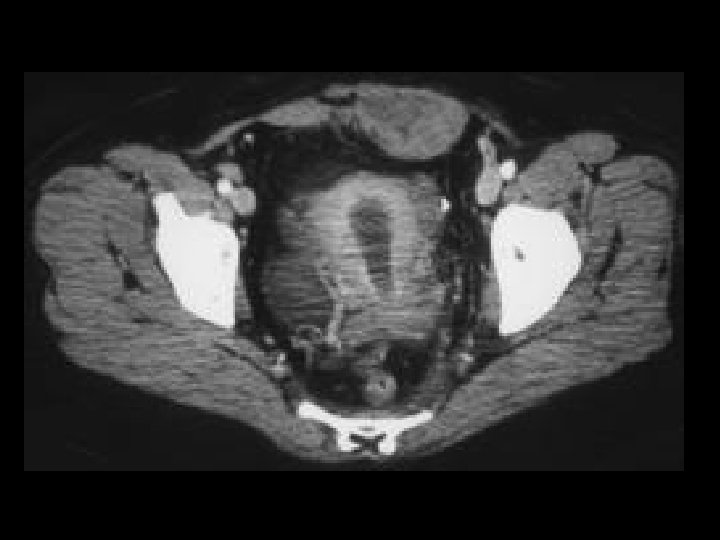

Bladder TCC • Findings: – Diffuse wall thickening of the bladder • ddx: – Underdistension – Muscular hypertrophy from outlet obstruction – Cystitis